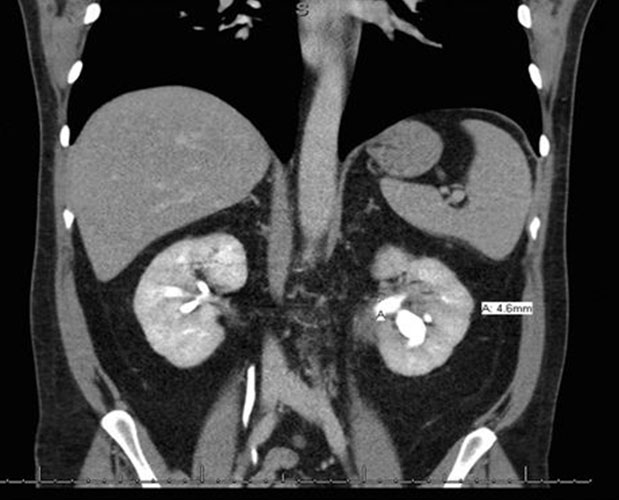

Two days later, he was referred to hepatology clinic for further workup. A trial of empiric prednisone, dosed at 40 mg twice per day, was started on account of concerns for IAC. The pathology results showed reactive epithelia only, without malignancy, and negative for FISH, IgG, and IgG4 stains. He returned to hepatology clinic three weeks later reporting resolution of all of his previous symptoms since initiation of prednisone. All his liver chemistry had improved to normal. The repeat CT scan showed improvement in the mass-like thickening of the CHD, now measuring 9 mm by 4 mm (Figure 4), with improvement in the urothelial thickening and resolution of the hydronephrosis. His prednisone was decreased to 40 mg once a day and thereafter to 30 mg once per day (Figure 5). Three weeks later he continued to be asymptomatic, and a repeat CT scan showed improvement in the mass size, continued CHD wall thickening, and resolution of his biliary ductal dilatation. A repeat EUS and ERCP done three weeks after the scan demonstrated resolution of the hilar mass and marked improvement of the CHD structuring, and the stents were removed. Brushings from the hilum were negative for malignancy. A month later, the patient started complaining of weight gain, muscle aches, and insomnia. The prednisone dose was then tapered to 20 mg per day and mycophenolate mofetil (MMF) 500 mg twice per day was added to his regimen. He continued to remain asymptomatic, liver chemistry tests remained normal, and repeat CT scans showed overall improvement in his CHD wall thickening (Figure 6). He continued to feel well on this regimen and denied any complain.

Figure 4: CT image showing improvement in the size of the CHD mass after initiation of steroids, now measuring 9 mm by 4 mm. CHD: common hepatic duct; CT: computed tomography.

Figure 5: CT image showing marked improvement in bilateral urothelial thickening after initiation of prednisone, with persistent left hydronephrosis measuring 4.6 mm. CT: computed tomography.